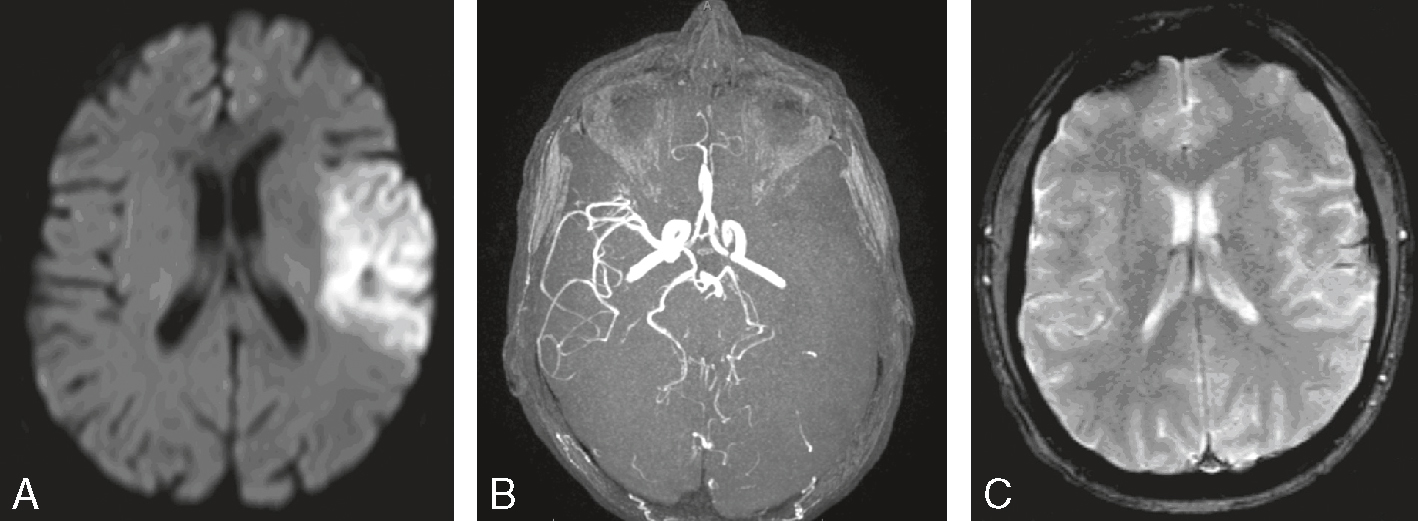

Une IRM encéphalique est réalisée (fig. 31.7). Sur cette planche, quels sont les éléments évocateurs du diagnostic de sclérose en plaques (SEP) ?

L'image montre trois coupes transversales d'un cerveau humain prises par imagerie par résonance magnétique (IRM). Chaque coupe est étiquetée avec des informations spécifiques : "FH 14 head", "FH 20 head" et "FH 26 head". Ces étiquettes indiquent probablement différentes sections ou niveaux de la tête. Les images montrent des zones de signal hyperintense, qui apparaissent comme des taches blanches sur les images. Ces zones peuvent indiquer des anomalies telles que des lésions, des plaques ou d'autres types de pathologies cérébrales. Les coupes transversales permettent de visualiser différentes parties du cerveau, y compris les ventricules cérébraux et la matière blanche environnante. Les images sont intéressantes car elles permettent de détecter et de surveiller des conditions neurologiques, d'évaluer l'étendue des dommages et de planifier des traitements appropriés. Les variations dans les images peuvent fournir des informations cruciales sur la progression de la maladie ou l'efficacité des interventions thérapeutiques.

- A 585présence d’hypersignaux de la substance blanche

- B localisation surtout périventriculaire des hypersignaux

- C aspect arrondi des hypersignaux

- D présence de trous noirs

- E atrophie cérébrale marquée